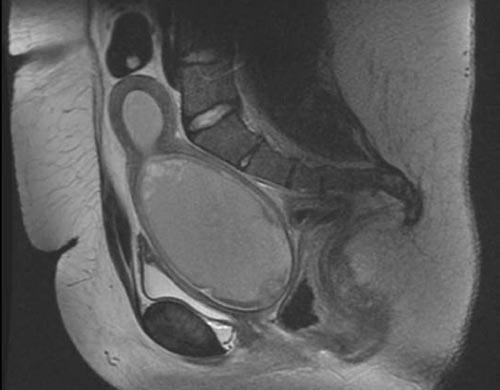

A healthy one-month-old girl has lower abdominal distention. An ultrasound demonstrates a cystic mass behind the bladder. Follow up MRI scan is shown. Physical exam reveals normal appearing genitalia with a single opening in the urethral position with no evidence of a vaginal opening. These findings are most consistent with:

3

The MRI scan shows evidence of a distended upper vagina and presence of a uterus which is most consistent with either a transverse vaginal septum or distal vaginal agenesis. Transverse vaginal septa are believed to arise from a failure in fusion or canalization (or both) of the urogenital sinus and Müllerian ducts. Many of the patients present at puberty with primary amenorrhea and a distended upper vagina. A complete transverse vaginal septum may be located at various levels in the vagina, but there is a higher frequency in the middle and upper third of the vagina. Transperineal, transrectal, and abdominal ultrasonography and MRI scan may be beneficial in establishing the diagnosis and determining the location and thickness of a transverse vaginal septum. Vaginal atresia occurs when the urogenital sinus fails to contribute to formation of the lower (distal) portion of the vagina. Mayer-Rokitansky syndrome is characterized by either partial or complete absence of the vagina and coexisting uterine abnormalities, with the uterus either partially or completely absent. In Mayer-Rokitansky syndrome, the fallopian tubes and ovaries are present but may be either normal or hypoplastic. Two types exist, type I that involves only the Müllerian structures (vagina and uterus) and type II that will involve concurrent abnormalities of either the cardiac, renal or otologic systems. Androgen insensitivity syndrome is characterized by the absence of a uterus, salpinx, and upper 2/3 of the vagina, these structures regress under the active influence of MIF secreted from the testes. CAH infant will manifest an enlarged clitoris and genital ambiguity, with variable lengths of a urogenital sinus present dependent upon the degree of androgen secretion from the adrenal glands. An imperforate hymen should demonstrate a visible bulging membrane at the vaginal introitus.